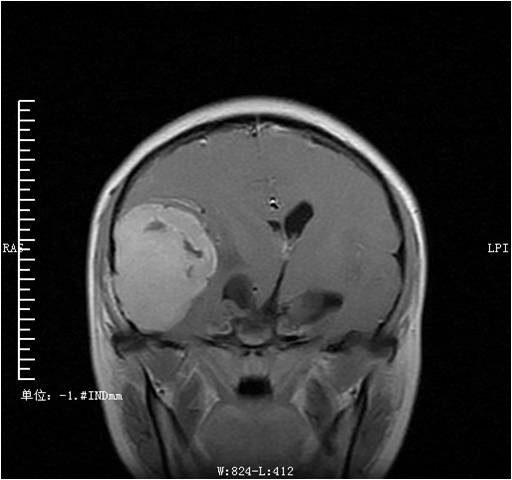

颅底脑膜瘤:病员因"头痛、头昏.左侧肢体无力4月。"门诊入院。患者体格检查:扶入院,急性痛苦貌. 神清合作,格拉斯评分E3V5M6 14分,双颞部压痛,无肿胀,双瞳孔等大等圆,直径约6mm,对光反射灵敏,左眼视力下降,距离眼30CM以内不能视物。鼻唇沟未见异常,伸舌居中,颈阻阳性。左侧上下肢肌力IV级,肌张力不高。膝反射、跟腱反射存在,右侧巴氏征、布氏征阴性左侧巴氏征、布氏征可疑阳性。辅助检查我院CT:急诊报告:1、右侧颞顶叶见一约7.6×4.5cm团块影,其内可见低密度区,右侧侧脑室受压,左侧侧脑室扩大,中线结构向左侧移位约1.2cm,右侧颞骨骨质破坏,疑右侧蝶骨受累,考虑占位性病变,性质?mri回:右侧颞部见一以宽基底贴近脑膜实性软组织肿块,大小约5.1X7.4X6.7cm,T1WI呈等信号,T2WI呈稍长T2信号,其内液化坏死区呈斑片状长T1长T2信号,增强扫描肿块实性部份显著强化,脑膜呈尾状强化,邻近颅骨骨质破坏,头皮下软组织见斑片状强化;肿块邻近脑组织受压塌陷,颞叶和右侧基底节区见斑片状水肿信号;右侧脑室受压变窄,左侧脑室后角和颞角扩张,中线结构向左偏移1.6cm。中脑受压变形。患者开颅病变切除术+颅内外减压术+硬脑膜修补术,术后予脱水降颅内压,营养神经,维持内环境,预防癫痫对症,请康复科予康复治疗

术前MRI: